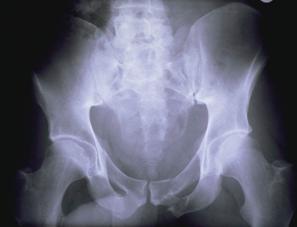

TRAUMATISMELE PELVIENE

Disjunctie de simfiza pubiana Disjunctie

de simfiza pubiana

Disjunctie sacro-iliaca stanga Disjunctie sacro-iliaca stanga. Aspect CT